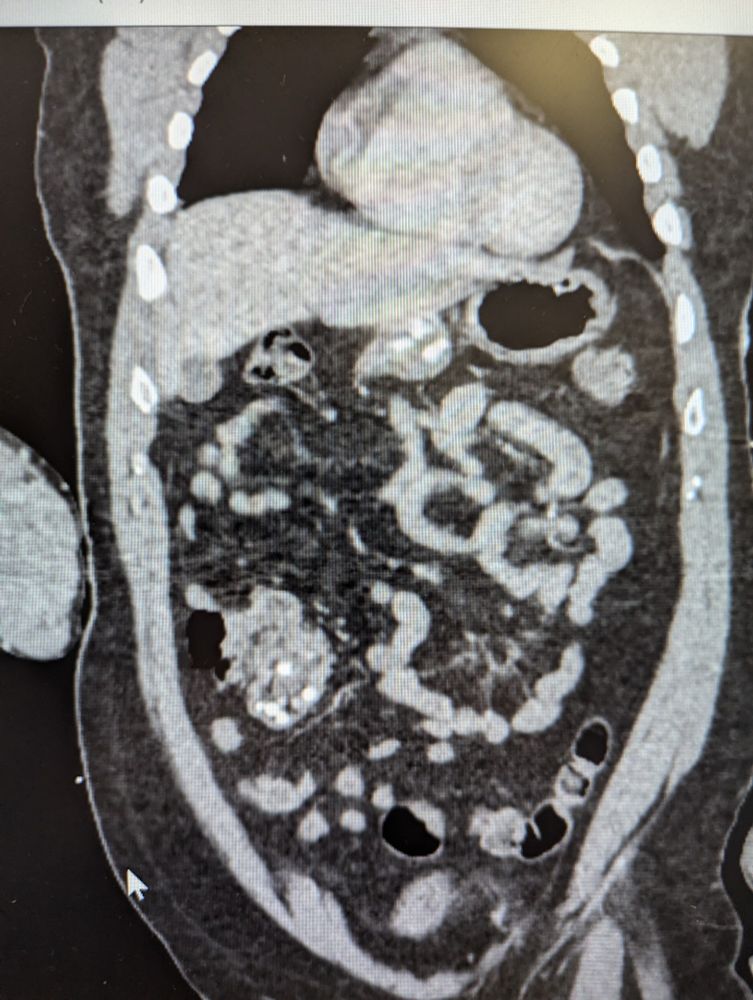

What did they eat ( duodenal and cecal) radio opaque fb)

#medsky

#emedsky

#radsky

#wtf